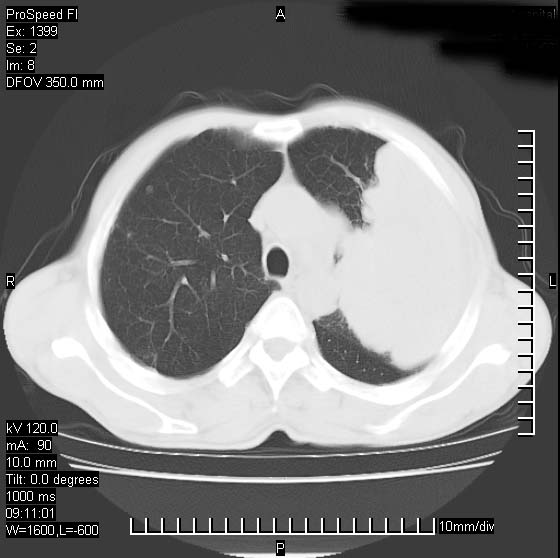

以下是引用卜一在2007-1-19 9:55:00的发言:[br]左肺沿胸膜下巨大肿块影,边缘呈分叶征,纵隔内见肿大淋巴结,右肺内另见一不规则结节影 .考虑:左肺周围性肺癌伴纵隔 右肺内转移.

以下是引用rgsyyf在2007-1-19 11:05:00的发言:[br]左肺上叶见形态不规则巨大软组织肿块影,边缘呈分叶征,纵隔内隆突下见肿大淋巴结,右肺内另见一不规则结节影 .考虑:左肺周围性肺癌伴纵隔即右肺内转移.